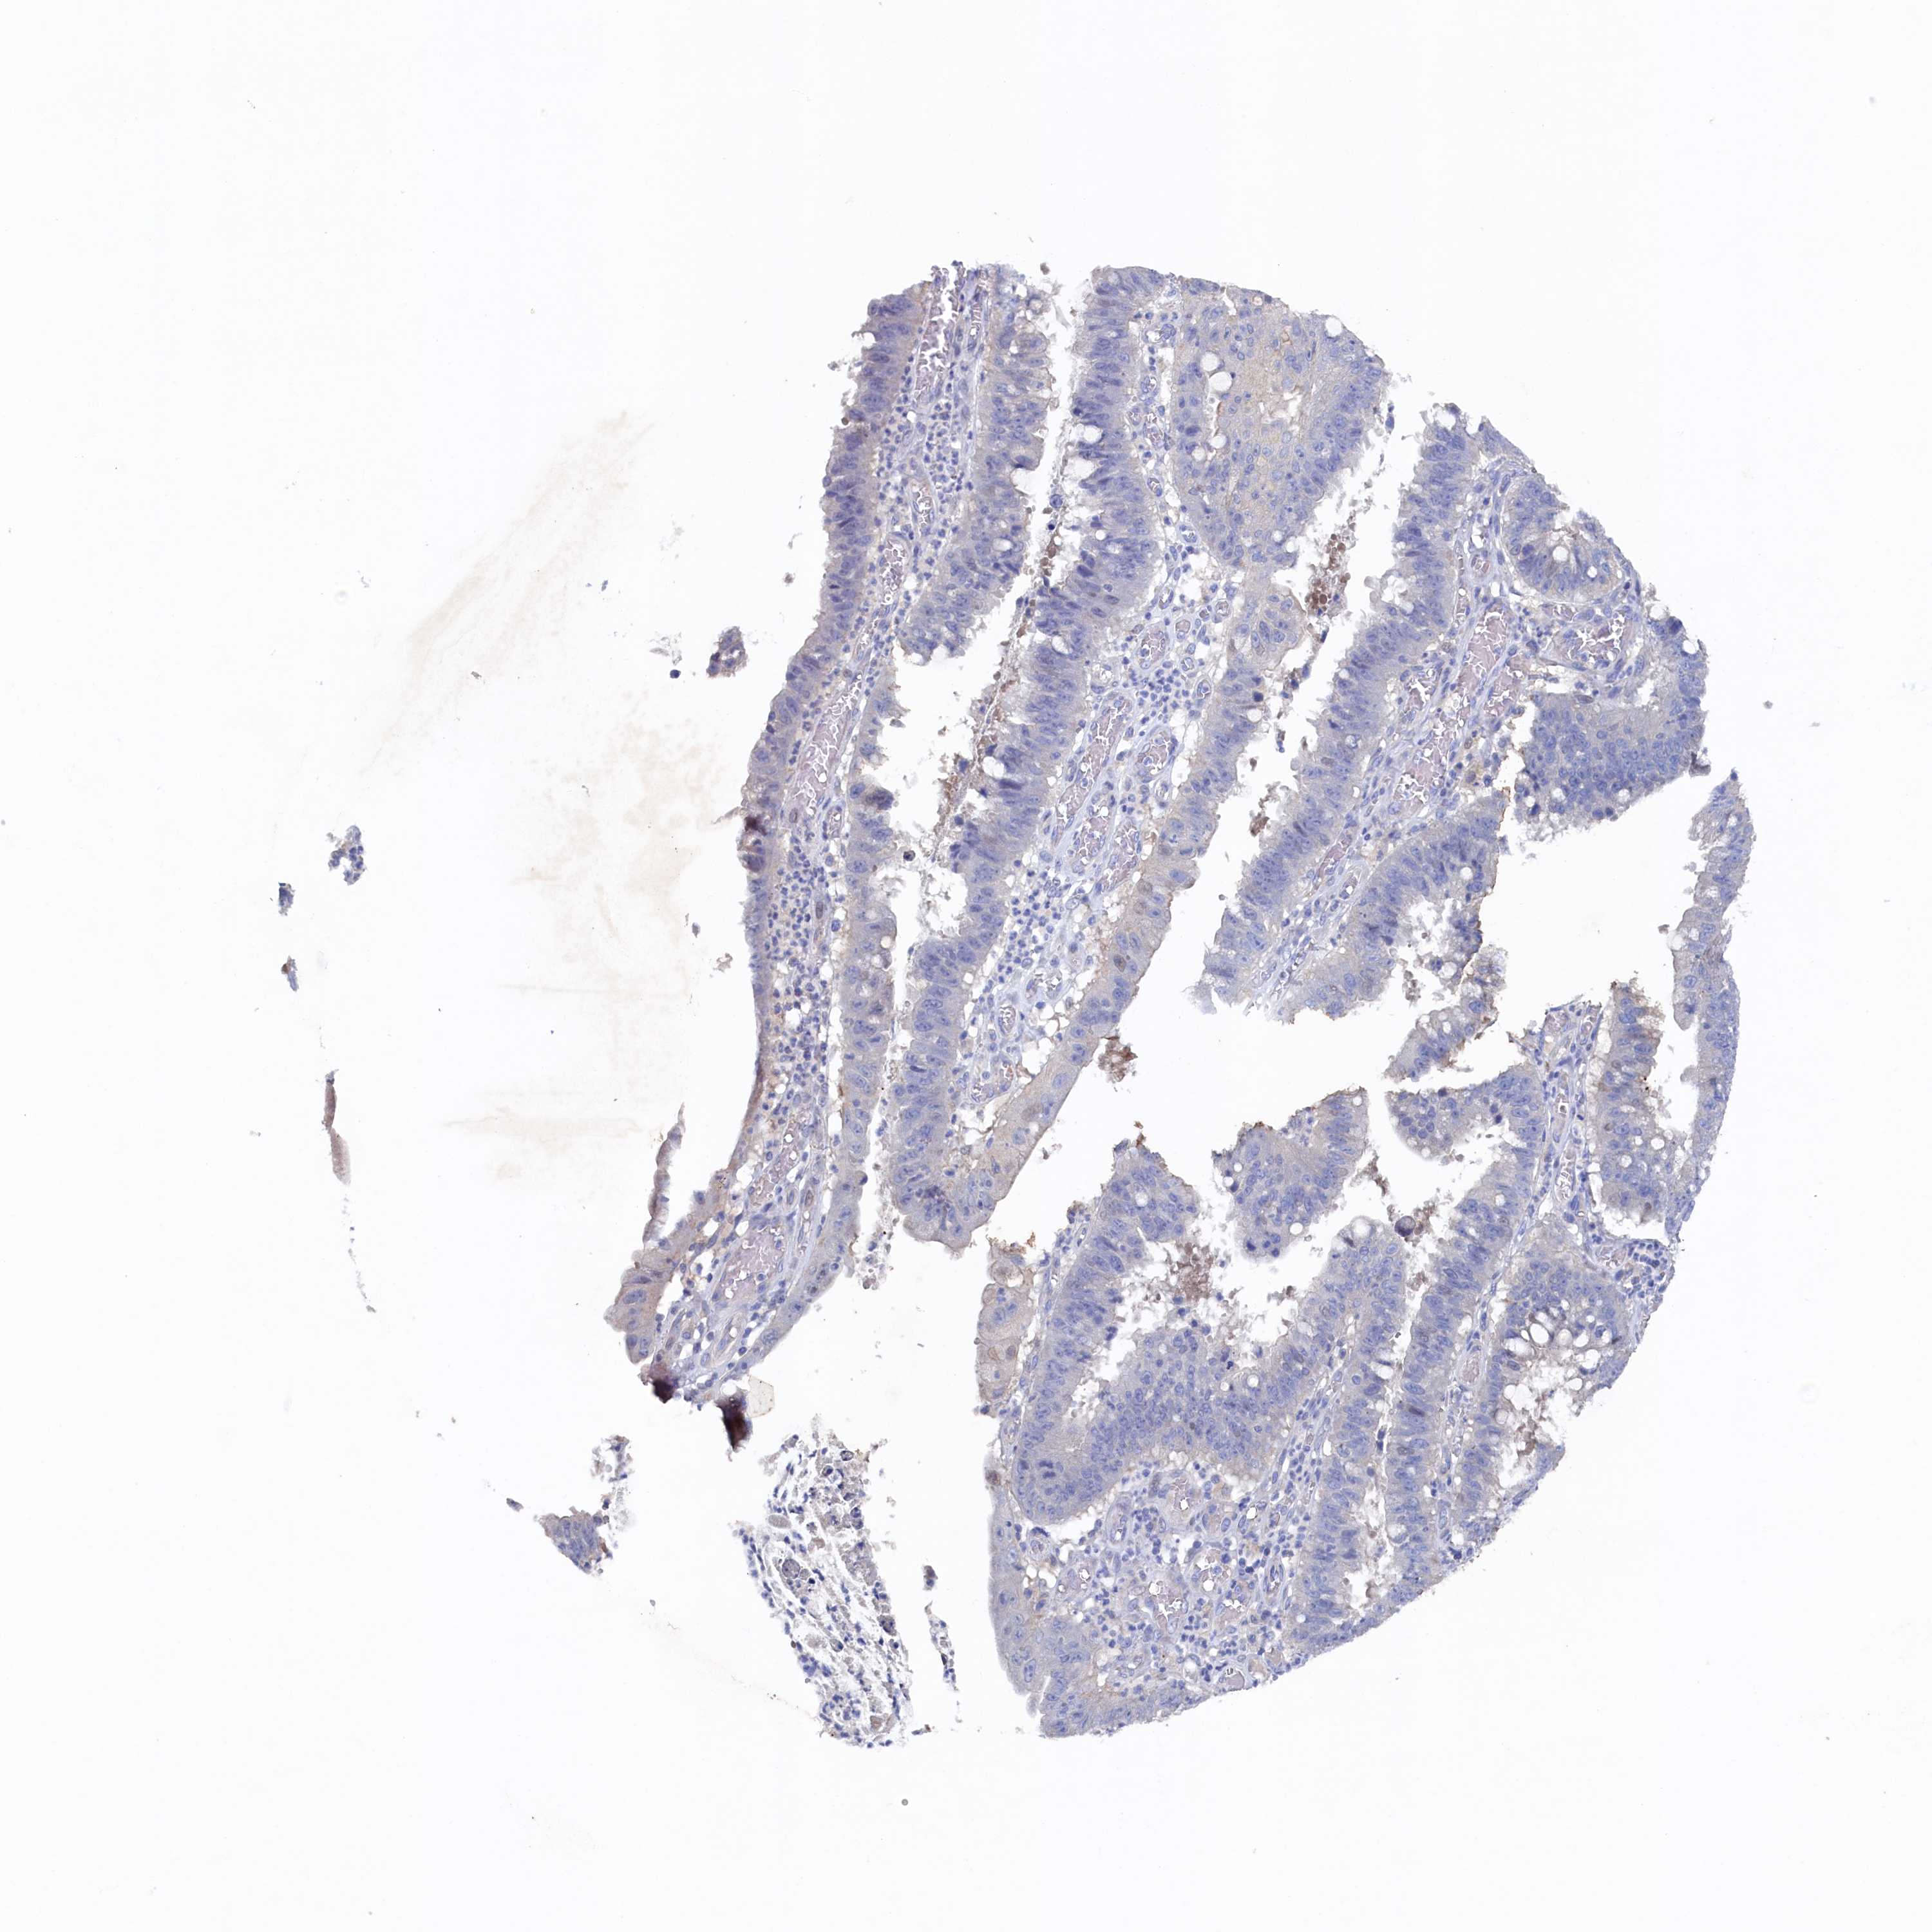

STOMACH CANCER - Protein expressioni

A mouse-over function shows sample information and annotation data. Click on an image to view it in a full screen mode. Samples can be filtered based on level of antibody staining by selecting one or several of the following categories: high, medium, low and not detected. The assay and annotation is described here.

Note that samples used for immunohistochemistry by the Human Protein Atlas do not correspond to samples in the TCGA dataset.

Antibody stainingi

Antibody staining in the annotated cell types in the current human tissue is reported as not detected, low, medium, or high, based on conventional immunohistochemistry profiling in selected tissues. This score is based on the combination of the staining intensity and fraction of stained cells.

Each image is clickable and will lead to virtual microscopy that enables deeper exploration of all samples and also displays staining intensity scores, fraction scores and subcellular localization as well as patient and tissue information for each sample.

Antibody HPA039908

Antibody HPA040774

Staining

High

Medium

Low

Not detected

Intensity

Strong

Moderate

Weak

Negative

Quantity

>75%

75%-25%

<25%

None

Location

Nuclear

Cytoplasmic/membranous

Cytoplasmic/membranous,nuclear

Adenocarcinoma, NOS

Adenocarcinoma, High grade